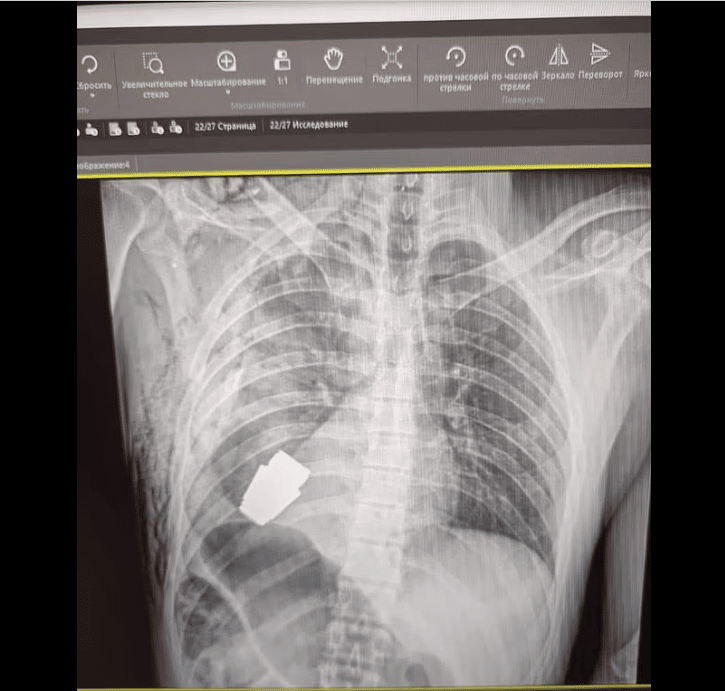

حالف الحظ والجهود الطبية أحد الجنود الأوكرانيين وبقي على قيد الحياة بعد أن استقرت قنبلة في جذعه خلال معركة في باخموت بأوكرانيا، وكان لابد من التدخل لإزالتها جراحيًّا.

القنبلة كانت معرضة للانفجار

واضطر الجراح الأوكراني اللواء أندري فيربا، إلى إجراء الجراحة علمًا أن القنبلة اليدوية يمكن أن تنفجر في أي لحظة.

وقال حاكم المنطقة، سيرهي بورزوف: أطباؤنا العسكريون أجروا عملية لإزالة قنبلة من جسد جندي، وخلال العملية كان من المستحيل إجراء التخثير الكهربي، وهي عملية جراحية تستخدم الحرارة للتحكم في النزيف وتدمير الأنسجة المتضررة؛ لأنها قد تؤدي إلى انفجار القنبلة.

حالة الجندي المصاب

ومع ذلك، قال بورزوف: إن الدكتور فيربا كان قادرًا على إجراء الجراحة بنجاح وإزالة القنبلة اليدوية، مضيفًا: التدخل العملياتي كان ناجحًا وتم إرسال الجندي المصاب لإعادة التأهيل والتعافي.

وأفادت صحيفة ديلي ميل أن الدكتور فيربا، أحد الجراحين الأكثر خبرة في أوكرانيا، يعمل في منطقة دونباس منذ عام 2014، حصل على جوائز الدولة للدكتوراه الفخرية في أوكرانيا ودكتوراه في العلوم الطبية وقاد الآلاف من العمليات الميدانية.